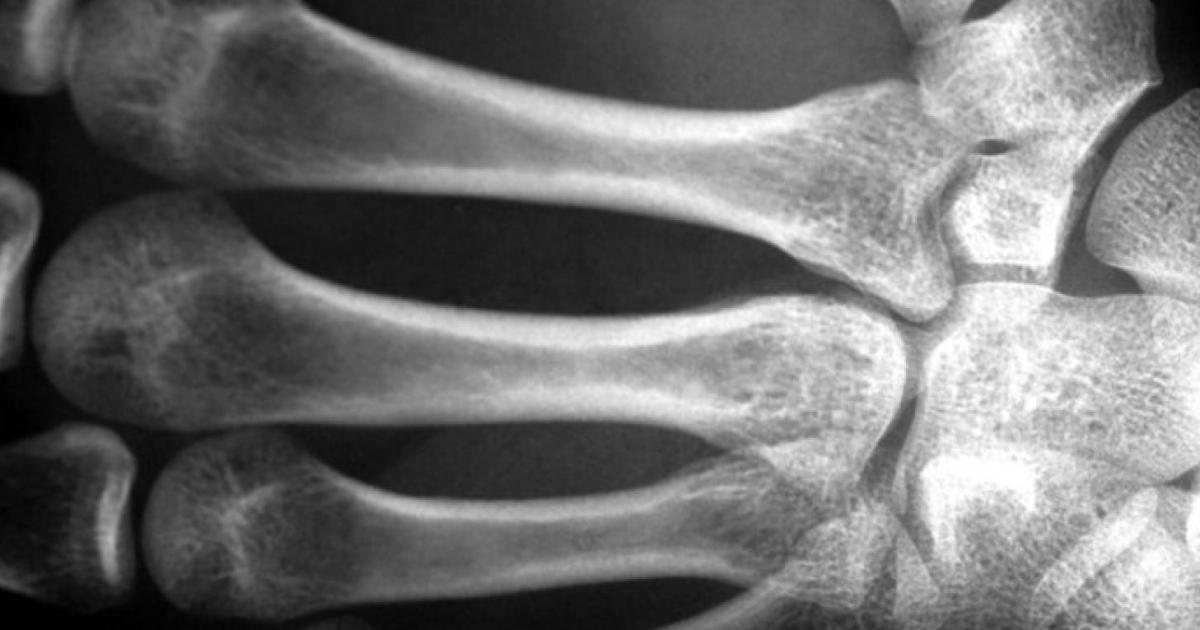

The National Spine Health Corporation in the United States estimates that two million men with osteoporosis, which means that the bones become porous and gradually losing their density and strength, which exposes individuals at greater risk of bone fractures, even from simple fall.

16 million men suffer from osteopenia, a condition in which the density of minerals in the bone decreases from natural reference values, but it is not low enough to comply with the criteria for diagnosing osteoporosis.